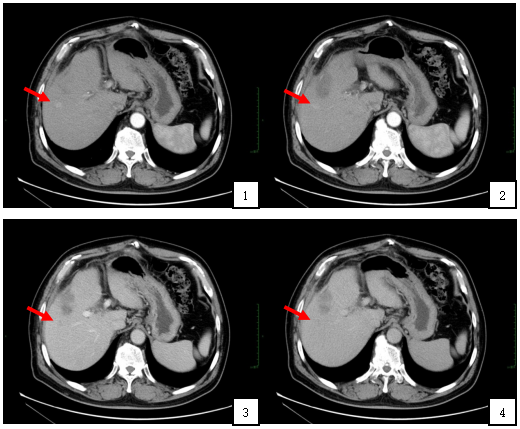

上腹部增强CT(门诊2019-3-20)结果回报:肝右叶强化结节,结合病史,考虑新发病灶;肝内多发局灶灌注异常,建议3-6个月复查;肝内囊肿,双肾囊肿;胆囊切除术后改变。

附图2:腹部增强CT显示:动脉期(图1,2)肝右叶可见高密度强化结节,直径约1.2cm,位置如箭头所示;静脉期和延迟期(图3,4)肝右叶结节呈低密度改变,位置如箭头所示。

1. 2019-3-28给予TACE治疗

附图3:肝动脉造影+栓塞术:肝动脉造影显示肝右叶近膈顶部可见肿瘤染色(图1箭头所示),导管超选至肝右动脉肿瘤供血血管,经导管注射碘化油约2ml,再次造影,可见肿瘤染色消失,有异常碘油沉积(图2箭头所示)。